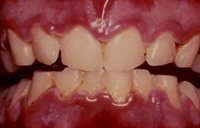

La gingivite ulcéro-nécrotique, également appelée angine de Vincent, doit être traitée en première intention avec des bains de bouche à l’eau oxygénée 3 vol%, à l’isobétadine buccal et des antidouleurs.

Necrotizing Ulcerative Gingivitis